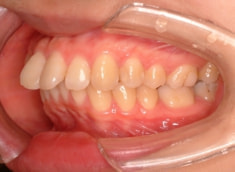

治療後(1年9ヶ月後)